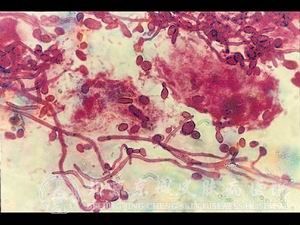

花斑癣症状具有哪些季节特点?北京京城皮肤医院的汗斑专家说,花斑癣症状一般是在夏天发病,冬天花斑癣症状不明显。在夏天的时候会在患者的面颈、腋下、胸背等汗腺丰富部位出现淡褐色、灰白色的点状、小片状屑斑。现在我们就来详细了解花斑癣症状特点有哪些?